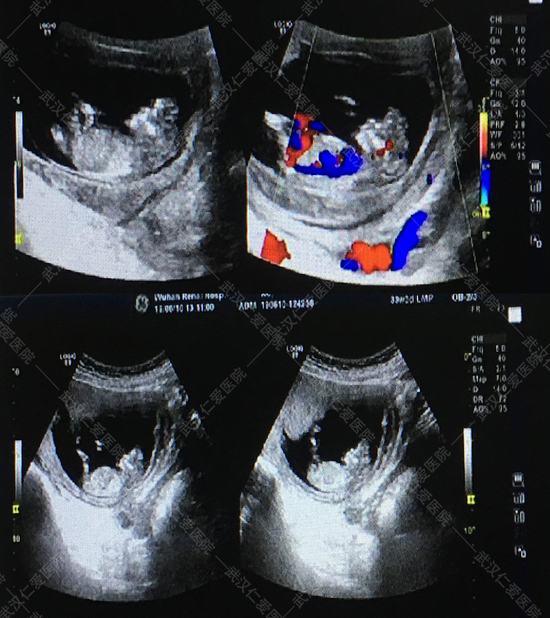

孕期NT檢查又稱頸后透明帶掃描,是孕檢項(xiàng)目中一項(xiàng)重要的檢查,也是最早排畸的檢查,可以在孕婦懷孕初期檢測(cè)出胎兒的發(fā)育狀況,有無(wú)畸形等,所以這個(gè)檢查是很重要的,關(guān)乎···